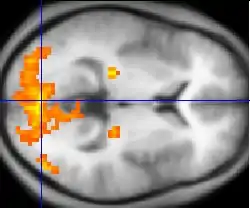

| Functional MRI (fMRI) | Blood-oxygen-level dependent imaging | BOLD | Changes in oxygen saturation-dependent magnetism of hemoglobin reflects tissue activity.[29] | Localizing brain activity from performing an assigned task (e.g. talking, moving fingers) before surgery, also used in research of cognition.[30] | ![]() |

Functional MRI

Functional MRI (fMRI) measures signal changes in the brain that are due to changing neural activity. It is used to understand how different parts of the brain respond to external stimuli or passive activity in a resting state, and has applications in behavioral and cognitive research, and in planning neurosurgery of eloquent brain areas.[48][49] Researchers use statistical methods to construct a 3-D parametric map of the brain indicating the regions of the cortex that demonstrate a significant change in activity in response to the task. Compared to anatomical T1W imaging, the brain is scanned at lower spatial resolution but at a higher temporal resolution (typically once every 2–3 seconds). Increases in neural activity cause changes in the MR signal via T*

2 changes;[50] this mechanism is referred to as the BOLD (blood-oxygen-level dependent) effect. Increased neural activity causes an increased demand for oxygen, and the vascular system actually overcompensates for this, increasing the amount of oxygenated hemoglobin relative to deoxygenated hemoglobin. Because deoxygenated hemoglobin attenuates the MR signal, the vascular response leads to a signal increase that is related to the neural activity. The precise nature of the relationship between neural activity and the BOLD signal is a subject of current research. The BOLD effect also allows for the generation of high resolution 3D maps of the venous vasculature within neural tissue.